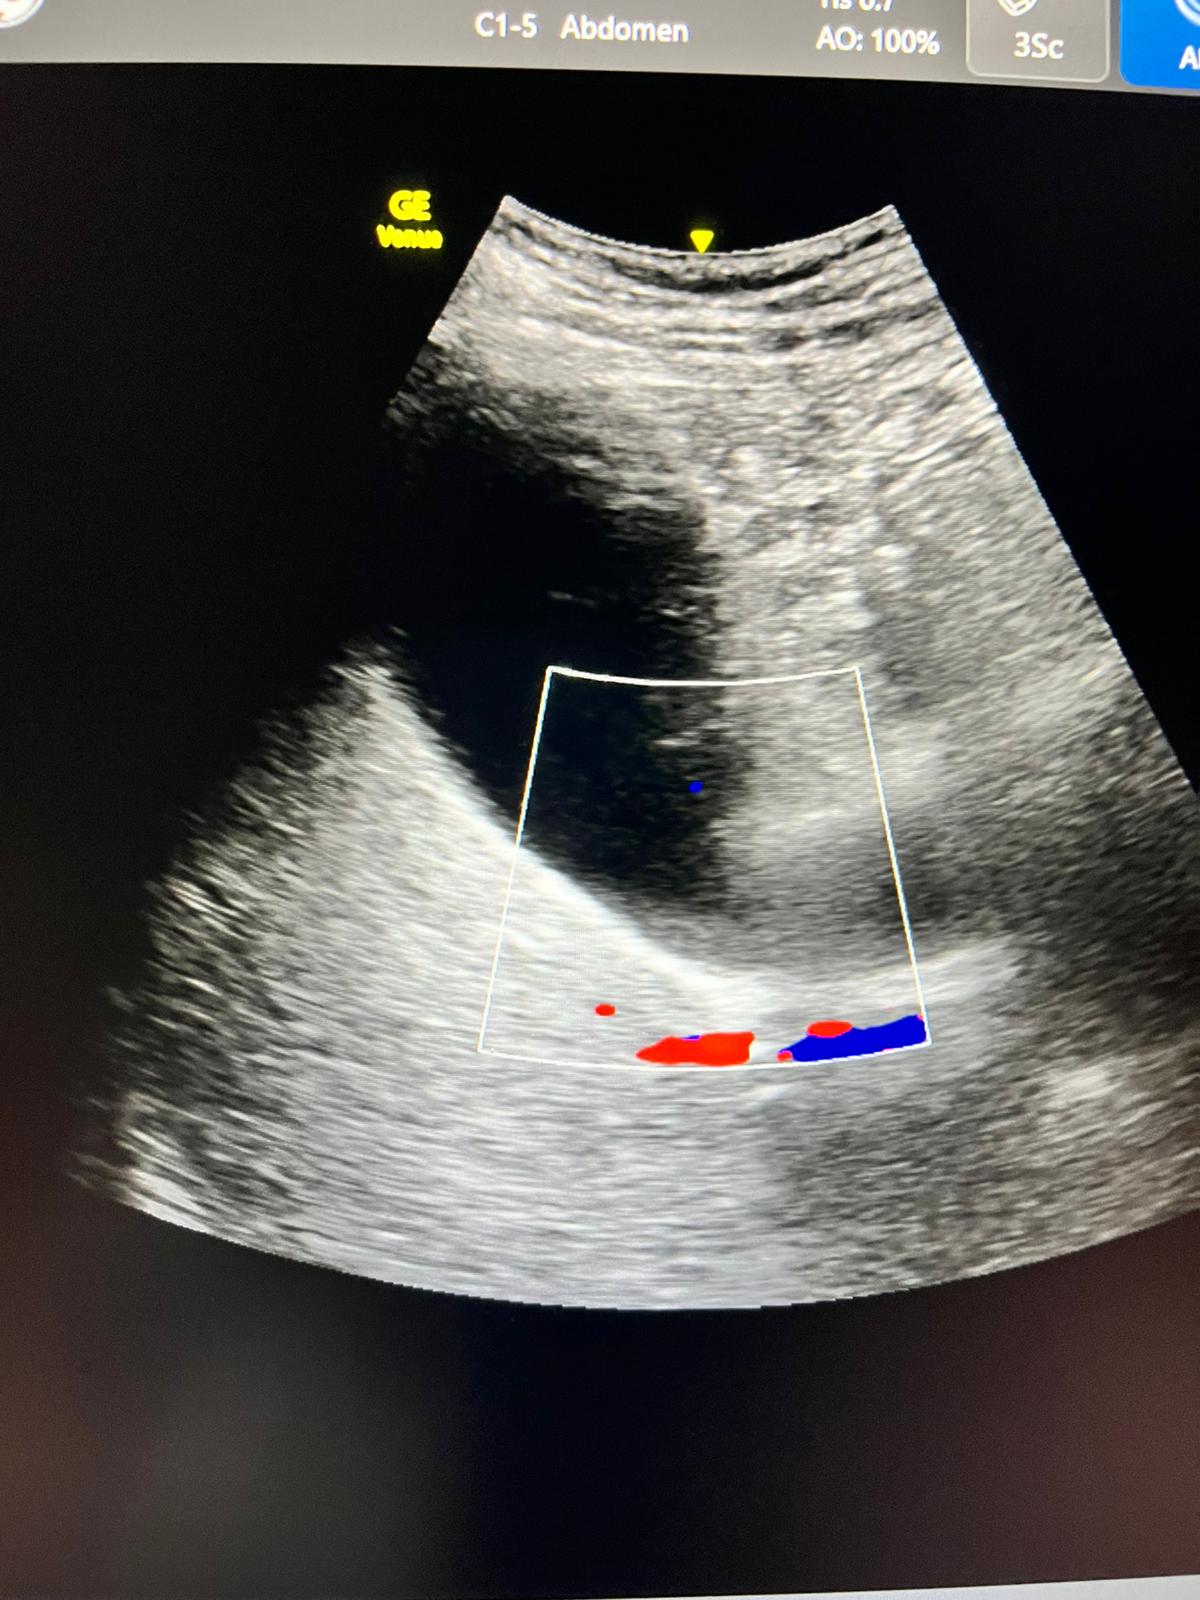

Ecografía: hígado y vías biliares normales sin formaciones expansivas. Coledoco de calibre normal.

Vesícula biliar distendida con litiasis múltiple suncentimétricas y barro biliar de paredes finas.

Páncreas y bazo sin alteraciones Riñones normales, sin dilatación de sistema excretor, urolitiasis ni lesiones expansivas sólidas. Quistes corticales simples en ambos riñones en tercio medio del izquierdo quiste complejo con tabiques finos y calcificación.